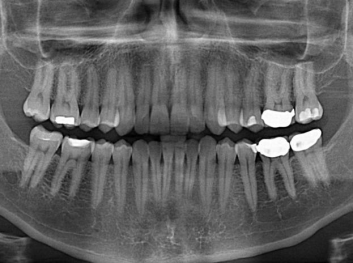

Adam Celiz,是來自諾丁漢大學(xué)的研究人員,他和同事開發(fā)的這種新型合成生物材料,能刺激干細(xì)胞在牙髓部的生長(zhǎng)。與普通材料一樣,這種合成材料被填充到牙齒并用UV光硬化。

在體外測(cè)試中,材料刺激干細(xì)胞進(jìn)入牙本質(zhì)的增殖和分化速度,促進(jìn)形成牙齒骨組織。研究人員認(rèn)為,一旦材料在受損牙齒中應(yīng)用,這些干細(xì)胞可以自動(dòng)修復(fù)來自填充物上的損壞。在本質(zhì)上,該生物材料將使牙齒自愈。